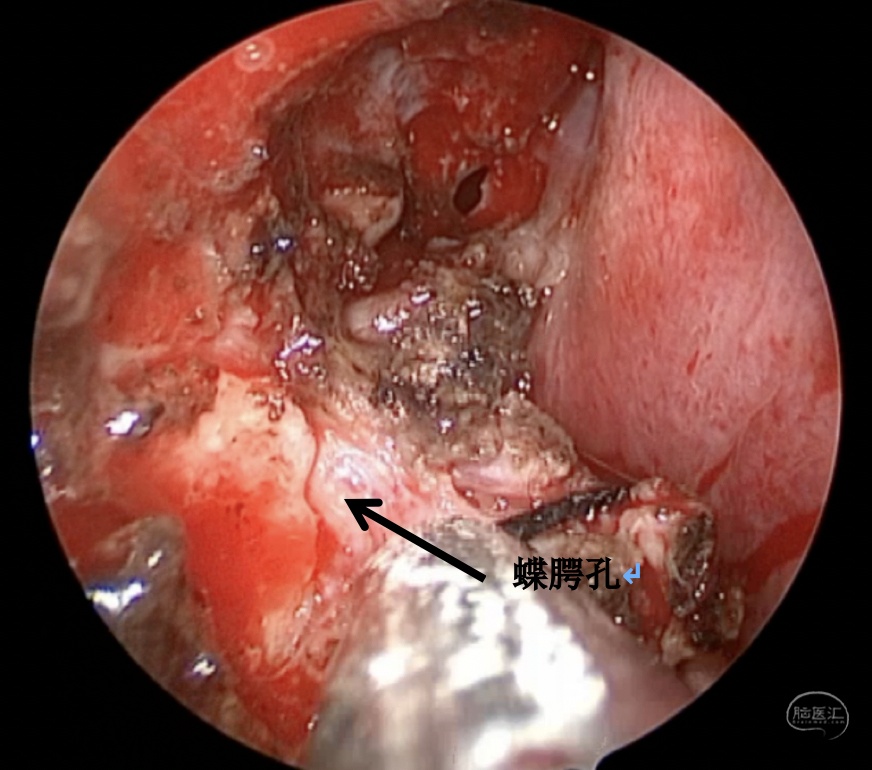

手术方案:内镜经鼻经翼突入路

术中情况:

蝶窦可向翼突根方向过度气化,位于翼管-圆孔连线之外的蝶窦腔隙,称作蝶窦外侧隐窝,是自发性脑脊液漏和脑膜脑膨出的高发区域。蝶窦外侧隐窝脑膜脑膨出伴脑脊液漏在临床上相对少见,这种脑膜脑膨出,如果在出生时出现往往较大,是因为在胚胎形成过程中,神经管未闭所导致。然而,较小的脑膜脑膨出可以多年都不被发现,或者由于外伤、医源性损伤、颅底侵蚀(炎症或者肿瘤)而发生。此外,由于各种原因的颅内压增高,迫使脑组织通过蝶骨的先天性薄弱区疝出,也可以导致该这种疾病发生,本例患者应属于这种情况。